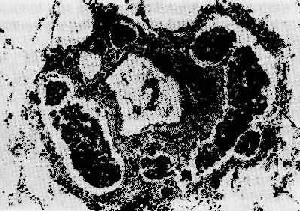

图7-4 恶性肿瘤的浸润性生长(食管鳞状细胞癌)

癌细胞形成大小、形状不一的细胞巢,浸润于管壁组织(包括肌层)间隙内